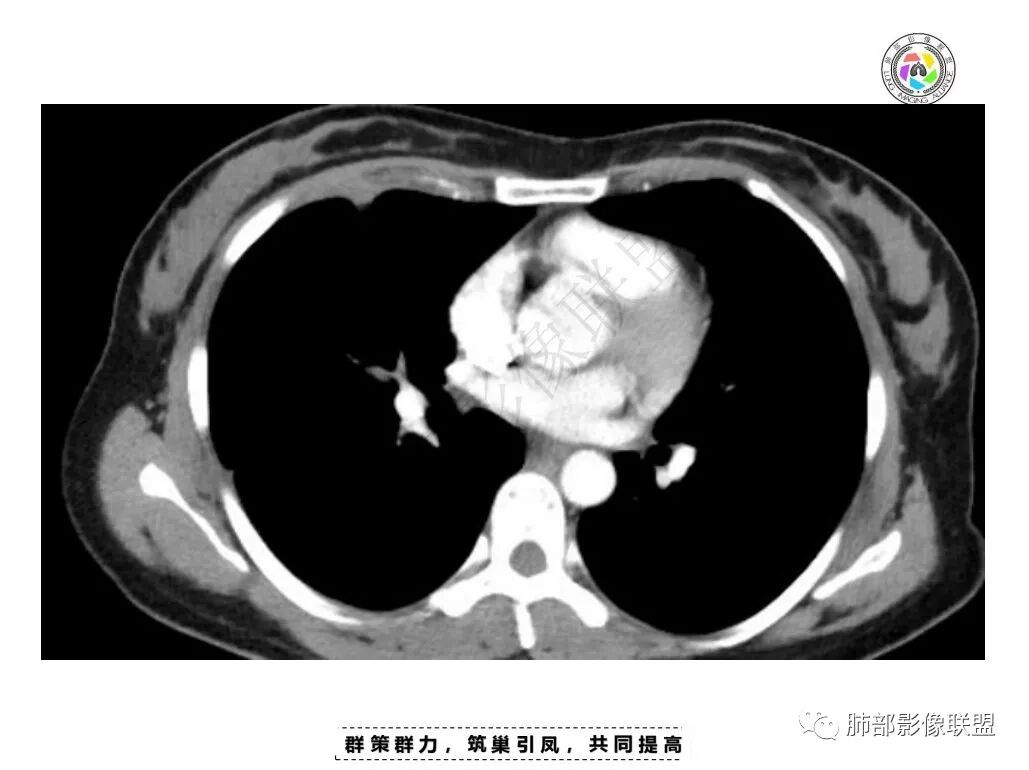

青年女性,慢性病程,右侧胸膜见两个结节,宽基底连于胸膜,临近胸膜增厚,胸膜下脂肪间隙消失,周围见片状高密度影,模糊不清,增强后不均匀强化,见坏死,抗结核治疗一个月,病变无明显变化,考虑结核,鉴别转移瘤

右肺中叶胸膜下结节,宽基底与胸膜相贴,胸膜顶起,密度不均,可见囊状低密度,强化明显,右肺下叶胸膜局限性增厚并向叶间裂延伸,考虑肋间神经鞘瘤,鉴别SFT

胸膜多个结节,附近胸壁脂肪间隙密度增高,提示有胸壁蔓延或侵犯。

胸膜区病灶周围肺内有小斑片状影,内有条索影,而非放射状,提示提示病灶累及肺内。周围渗出明显——良性肿瘤排除

1.胸膜多发结节,边缘比较光滑,累及胸壁(胸痛也符合,一年),表现为脂肪间隙密度增高,最大的病灶累及肺内,附近有渗出,但是无放射状表现,增强中央有坏死灶,一月后似有缩小,肋骨完整未见破坏,支持炎性可能大!